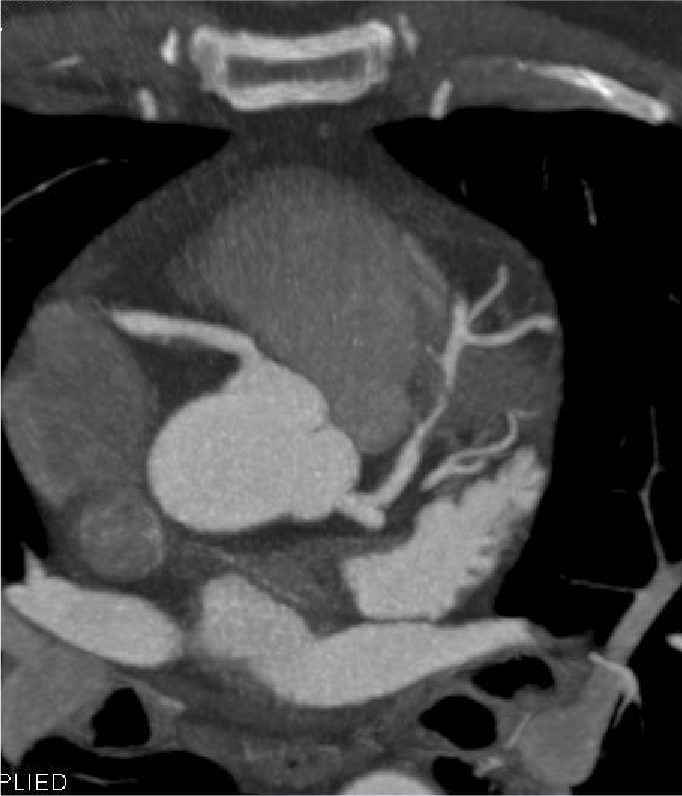

Tomografía cardiaca

Este estudio es adquirido con un tomógrafo de alta velocidad y baja radiación que permite evaluar las arterias coronarias y demostrar la ausencia o la presencia de placas ateromatosas, que son las que ocasionan un infarto (enfermedad arterial coronaria). Mediante la emisión de rayos X es posible obtener imágenes bidimensionales y tridimensionales del exterior y del interior de las arterias coronarias, del corazón y de la función cardiaca.

Cuando es necesario hacer una evaluación mas precisa de tus arterias coronarias la tomografía cardiaca permite, mediante la inyección de contraste por una vena del brazo, estudiar el interior de las arterias y demostrar si existen o no placas que impiden el paso de sangre hacia el corazón, a esta modalidad de la tomografía cardiaca le conocemos como angiotomografía coronaria, que se adquiere en 30 a 60 minutos, y es hoy día el estudio mas confiable para evaluar en forma no invasiva las arterias que nutren al corazón y que cuando se enferman pueden ocasionarte un infarto.